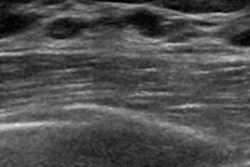

The company's DS Breast AI software was trained on nearly 1 million ultrasound images of both malignant and benign breast lesions from sources around the world and can be used as an on-demand second opinion.